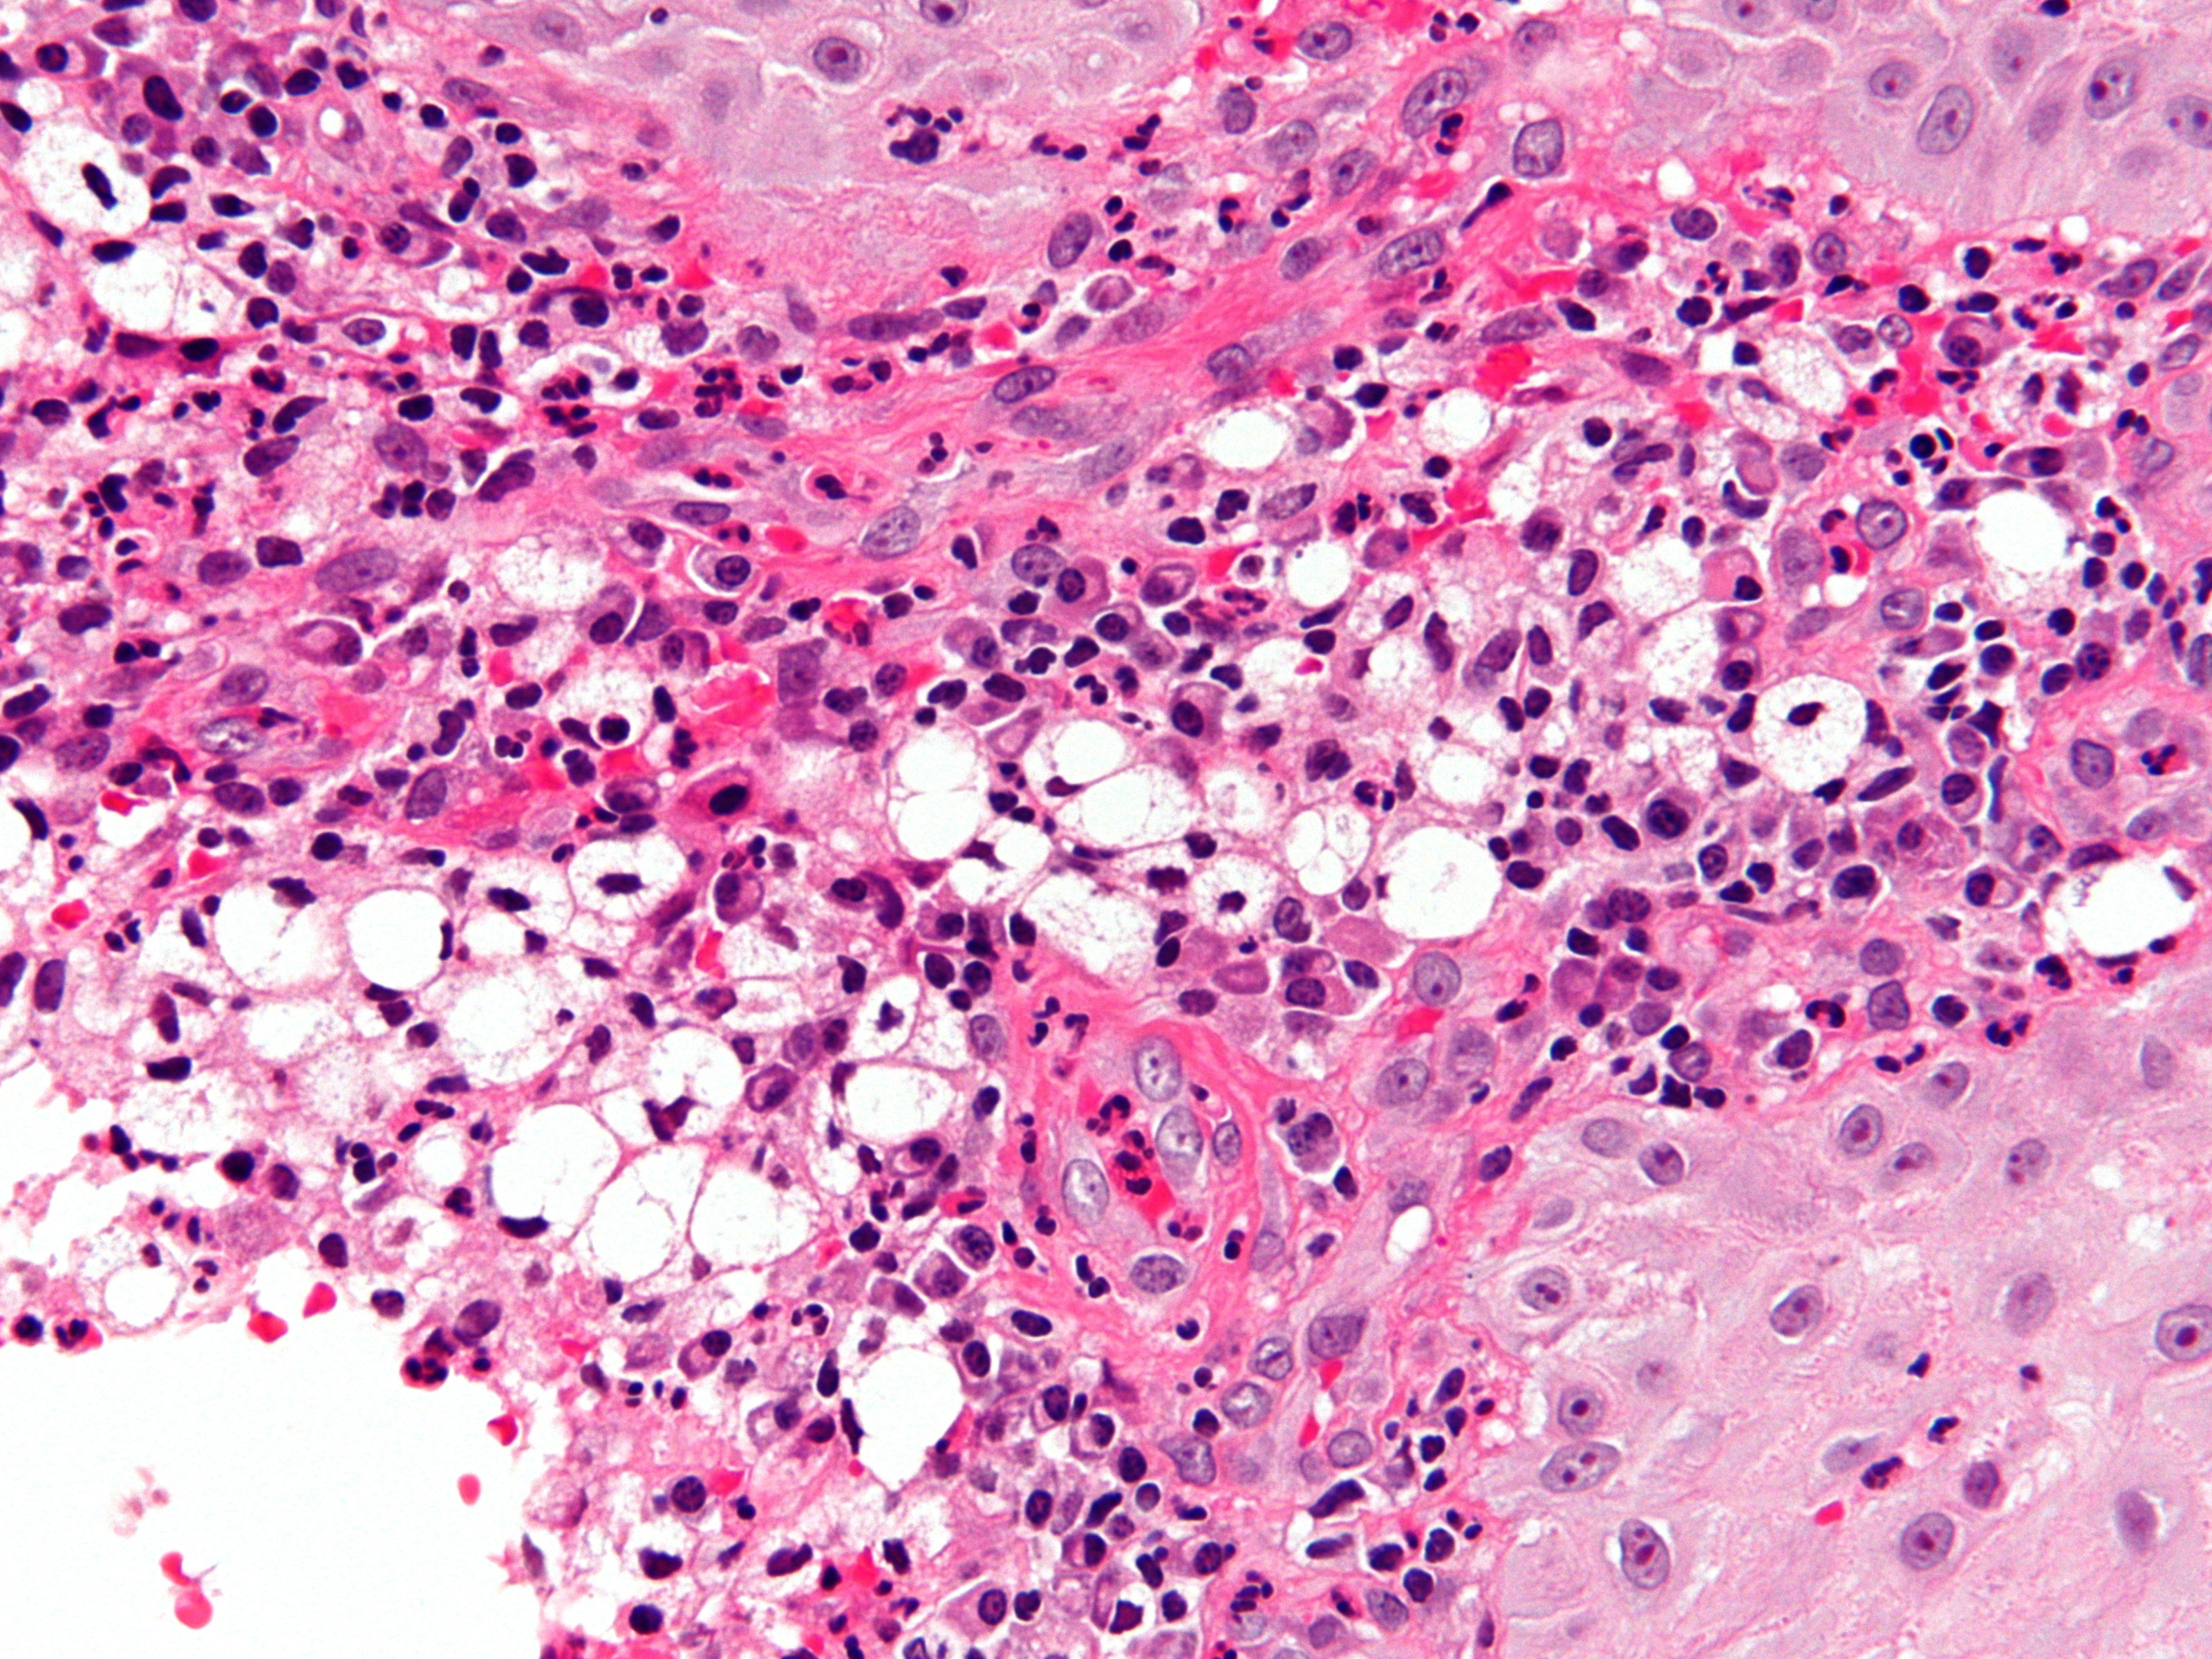

PA:Hyperplasie van het epitheel. In

het onderliggend stroma een gemengd infiltraat bestaande uit schuimige histiocyten

(Mikulicz cells), plasmacellen, lymfocyten, en neutrofiele leukocyten. Soms

multinucleaire cellen of histiocyten met eosinofiel cytoplasma (Unna cells).

Mikulicz cellen hebben een pyknotische centraal of perifeer gelegen kern en

een schuimig cytoplasma met cytoplasmatische vacuolen.